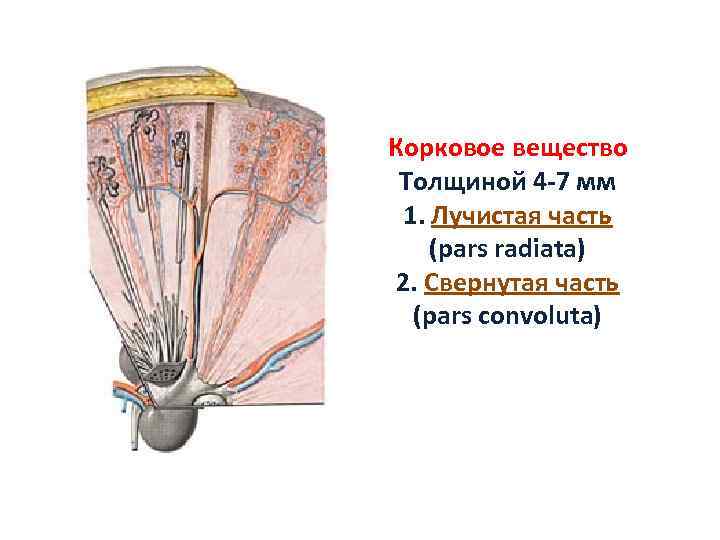

Корковое вещество Толщиной 4 -7 мм 1. Лучистая часть (pars radiata) 2. Свернутая часть (pars convoluta)

Корковое вещество Толщиной 4 -7 мм 1. Лучистая часть (pars radiata) 2. Свернутая часть (pars convoluta)